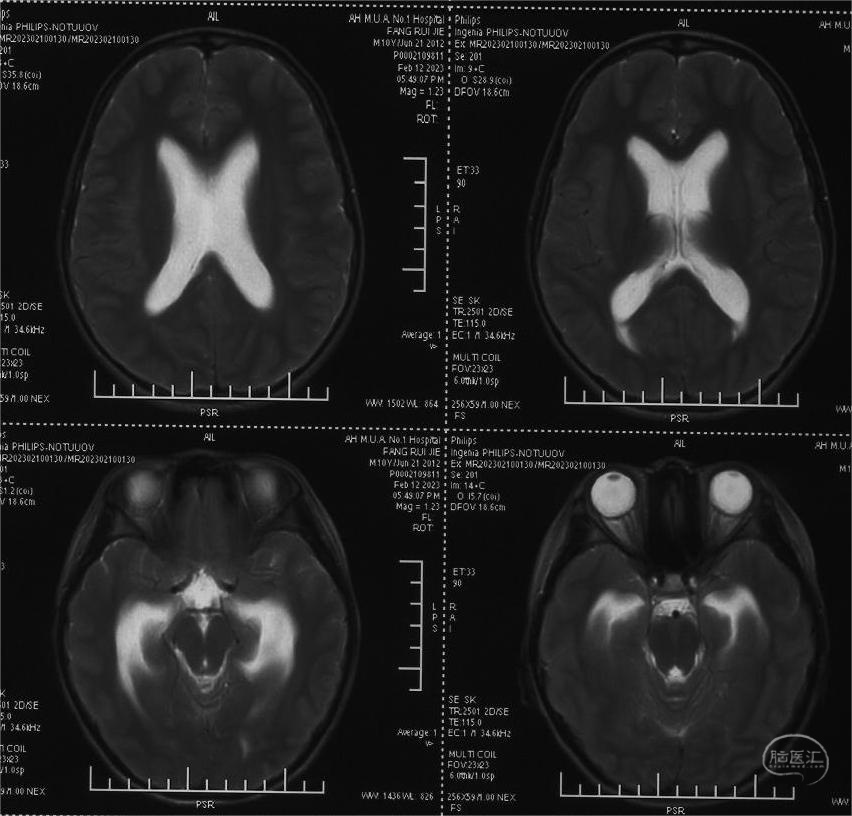

患儿方x,10岁9月,因“头痛、呕吐1月,外院行三脑室底造瘘术后2周”入院。患儿1月前无明显诱因下出现头痛,严重时伴有喷射性呕吐,就诊当地医院,检查发现松果体区占位、脑积水,行三脑室底造瘘术(图1)。术后患者头痛呕吐症状明显缓解,但新出现间断癫痫大发作,予以丙戊酸钠+氯硝西泮抗癫痫抗癫痫治疗,控制满意。就诊我院,神经系统查体未见明显异常。脑MRI检查提示松果体区占位(图 2A-C)。

图1,术前脑室稍扩大